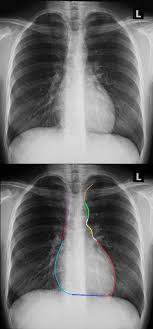

Evaluation of a chest radiograph may appear to be simple, but is in fact a complex task requiring careful observation, sound understanding of chest anatomy, and knowledge of the principles of physiology and pathology. Major structures are shown in fig. However, finding problems that are often a/w arrhythmias, such as cardiac enlargement and lung disease, should alter one to the possibility of arrhythmias. The interpretation of a chest film requires the understanding of basic principles. Conclusion of living anatomy of the chest congratulations!

Major structures are shown in fig.